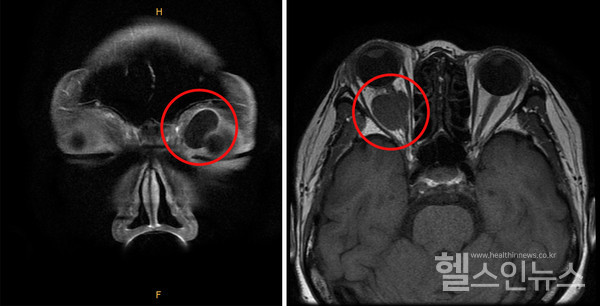

안와 양성 종양은 일반적으로 수술을 통해 제거할 수 있으나, 발생 위치에 따라 합병증 발생 위험이 있을 수 있으므로 신중하게 치료 방향을 결정해야 한다. 먼저 수술 전 CT 및 MRI 검사를 통해 종양의 크기, 위치, 성상을 정확하게 파악하고 분석한다. 안와 앞쪽에 위치한 종양은 상대적으로 쉽게 제거할 수 있다. 흉터 없이 제거하기 위해 쌍꺼풀 라인을 따라 절개하고 수술을 진행하기도 한다.

안와 뒤쪽에 위치한 종양도 종류에 따라 박리가 비교적 쉬운 종양도 있으나, 일부는 합병증 발생 위험이 있다. 특히 안구 뒤쪽으로 시신경이 뇌와 연결되는 구멍이 있는 ‘안와첨’은 좁은 공간 내 많은 신경과 혈관, 외안근 시작 부위 등이 가깝게 자리 잡고 있어, 종양 수술 후 합병증 발생 위험이 높아 수술 여부를 신중하게 검토해야 한다. 이에 안와첨 종양은 수술이 아닌 사이버나이프 같은 방사선치료를 통해 크기를 줄이는 치료를 시행하기도 한다.

안와 뒤쪽 공간에 종양이 발생하면, 종양의 크기가 꽤 커질 때까지 환자가 증상을 느끼지 못하는 경우가 많다. 시력이나 시야에 이상이 없고, 안구 움직임에도 영향을 주지 않는 양성종양의 경우 경과 관찰을 하는 것으로 치료 방향을 결정하기도 한다.